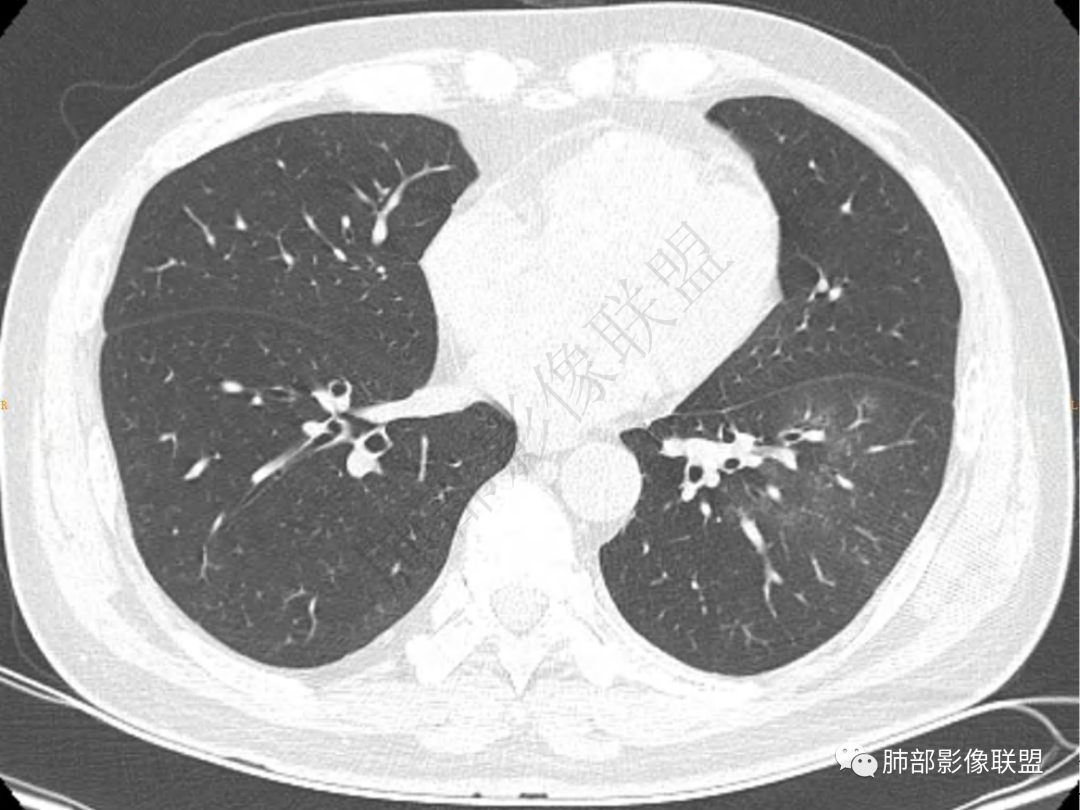

1.中年男性,咳嗽咳痰20余天,间断咯血2周

2.左肺下叶团片影,跨背段及内前基底段,实性部分类椭圆形,密度不甚均匀,可见毛刺及棘状突起,未见典型分叶及胸膜凹陷。病灶上下缘可见相应肺段支气管旁进侧出,管壁轻度增厚,未见狭窄阻塞。

3.周边较大范围磨玻璃影,边界相当模糊,小叶增厚明显。注意叶裂另一侧、左肺舌段亦可见磨玻璃影及增厚的小叶间隔。未见明确卫星病灶。

4.实性部分不均匀环形强化并显示一小范围低密度坏死区或空洞。较之肺窗,整体纵隔窗范围较小,提示病灶并不十分密实。抑或为不同时段图像。

5.双肺门及纵隔未见增大淋巴结。未见胸腔积液。